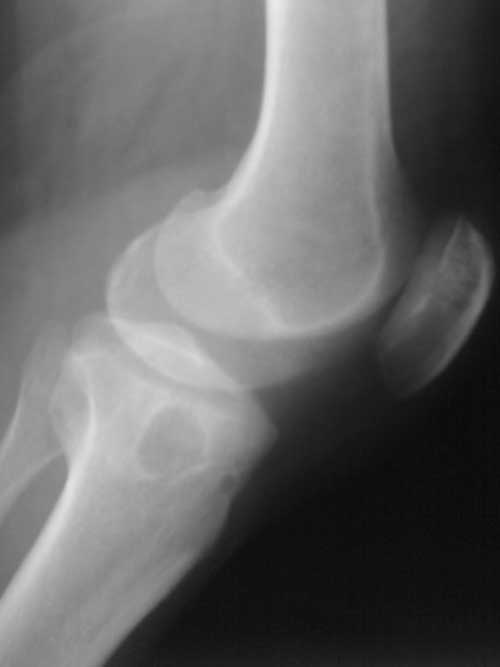

标题: X7063:女、40岁、左膝间歇性疼痛一年余,否认有外伤史。 [打印本页]

标题: X7063:女、40岁、左膝间歇性疼痛一年余,否认有外伤史。

1  左膝退变并关节面下骨质囊变。2 二分髌骨。

1)左膝关节退行性骨关节病,左胫骨上端邻关节骨囊肿。2 )二分髌骨。

邻关节骨囊肿或软骨下假囊肿,二分髌骨。

左膝关节退行性骨关节病,左胫骨上端骨囊肿。二分髌骨。

)左膝关节退行性骨关节病,左胫骨上端邻关节骨囊肿。2 )二分髌骨。